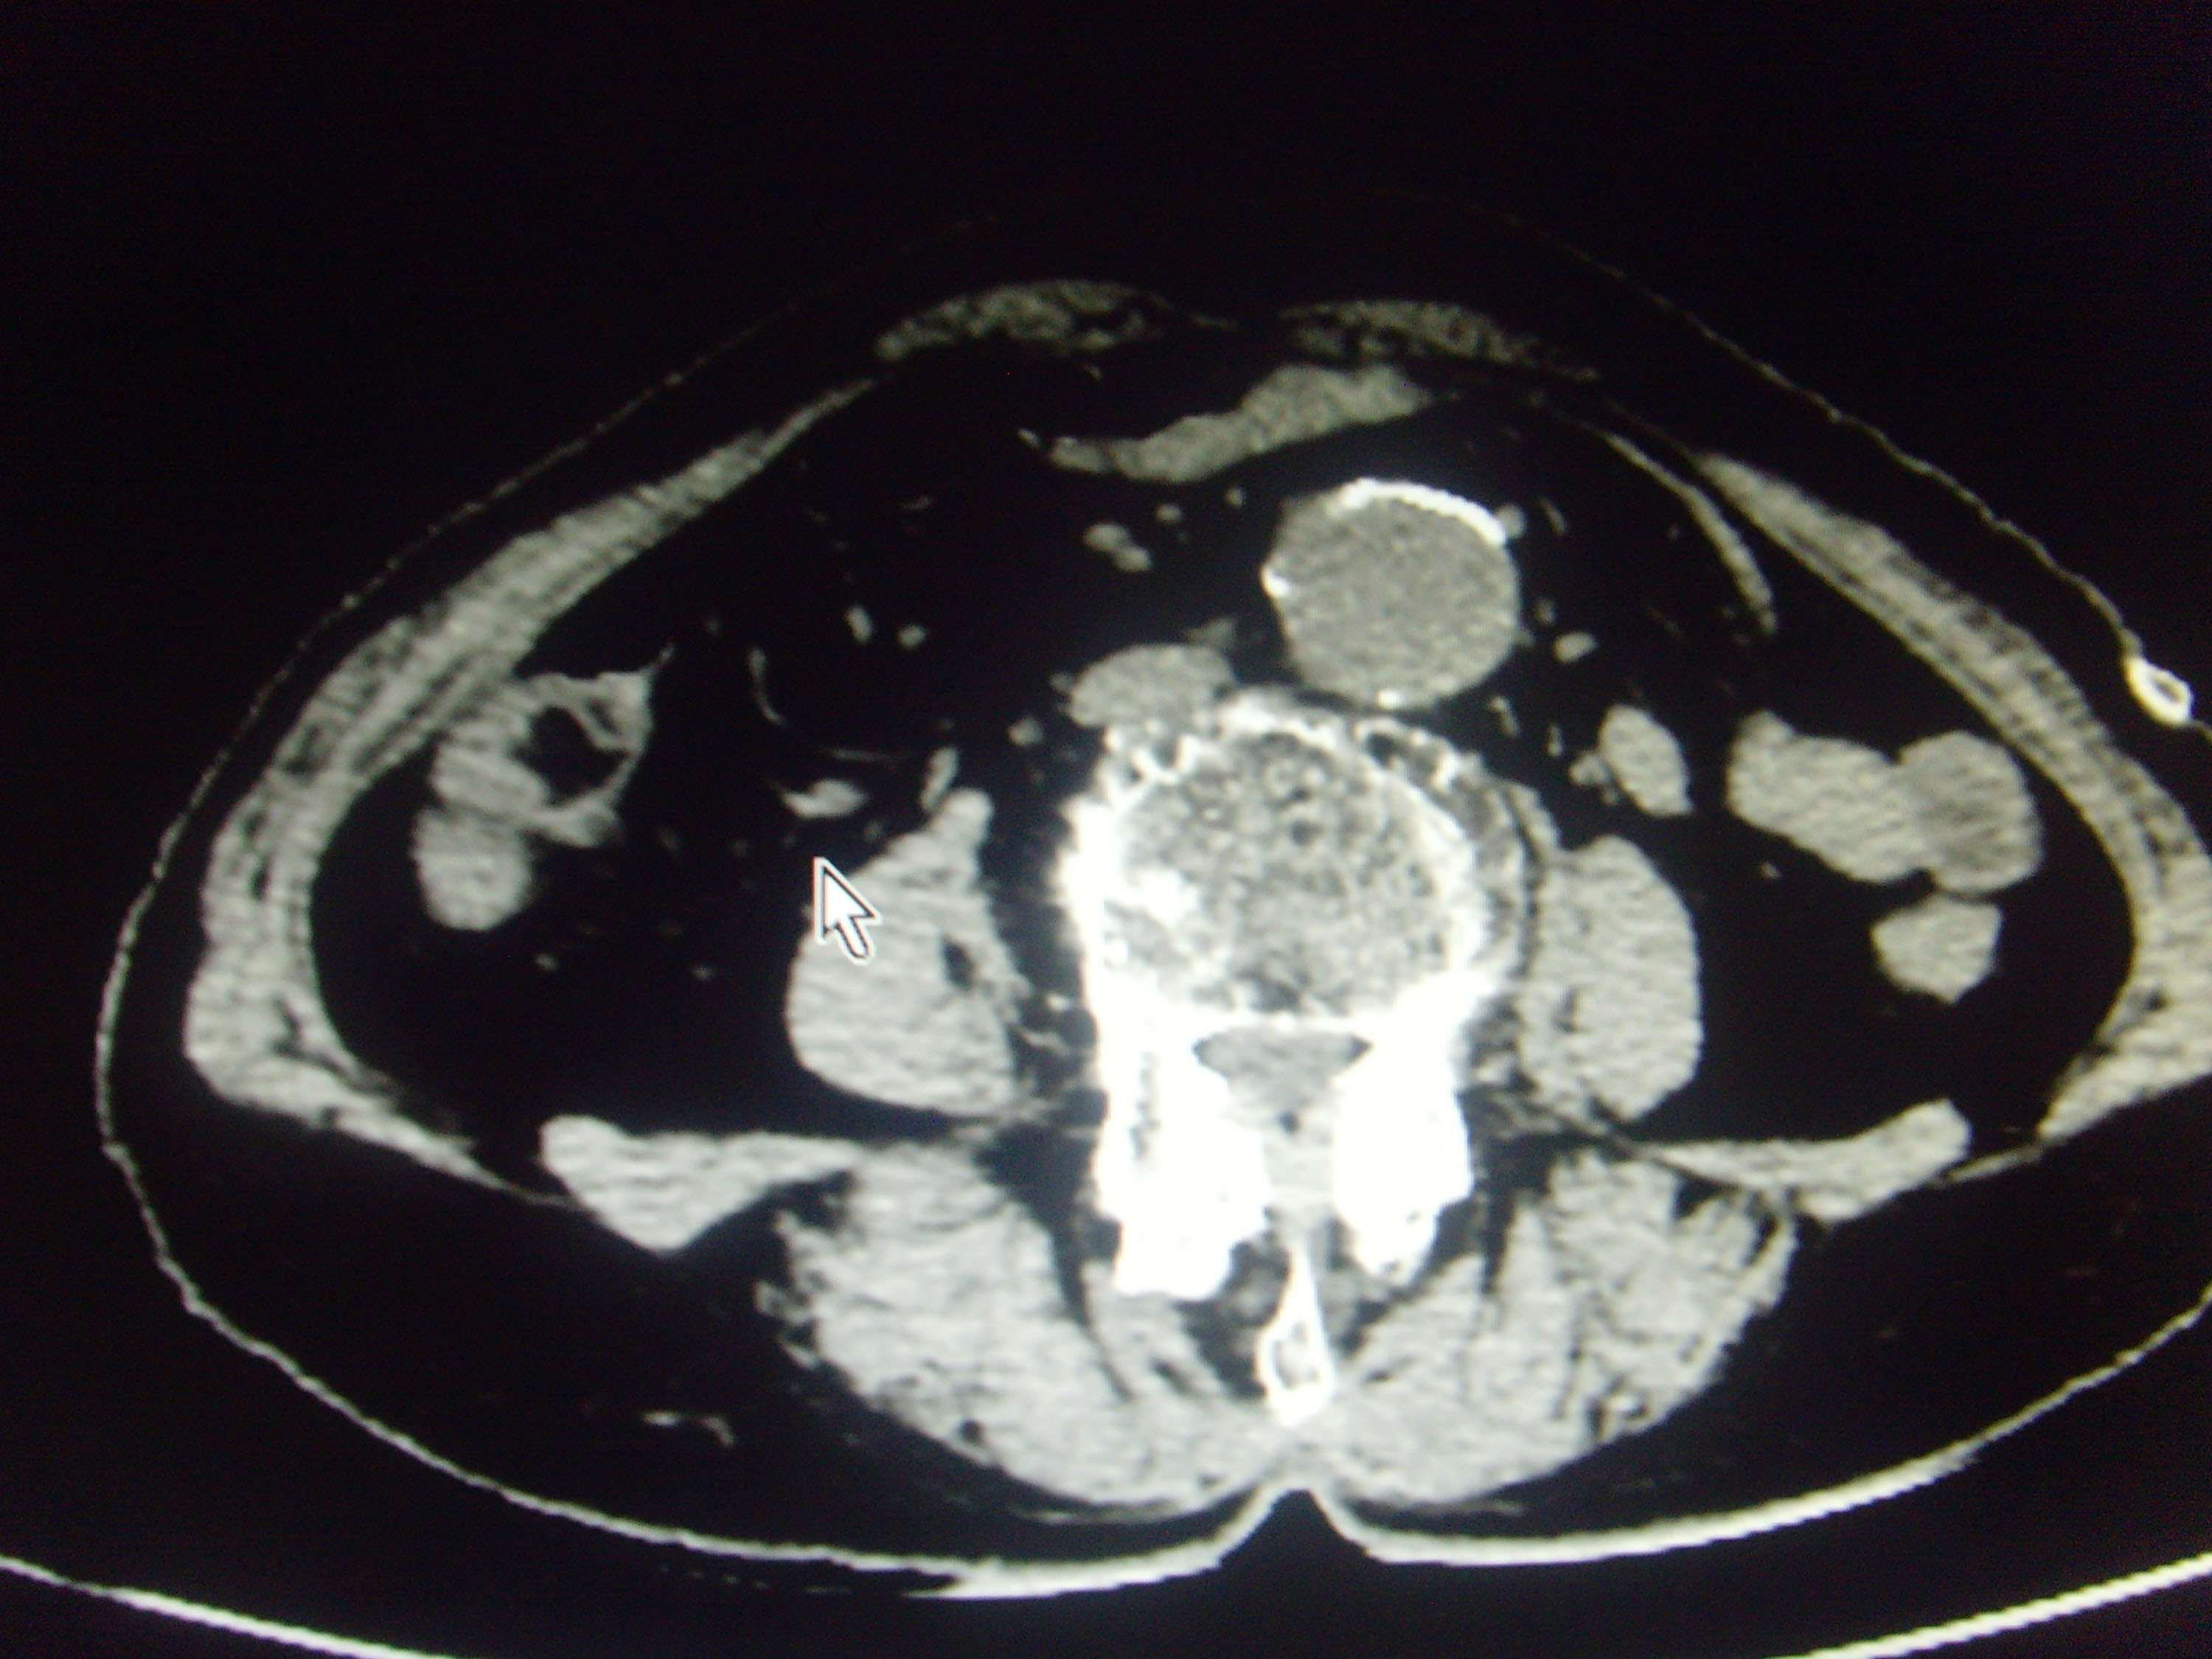

CT51913:腹主动脉夹层?

本帖最后由 cefcmj 于 2016-5-7 21:44 编辑 女,73岁,右下腹疼痛,腹主动脉夹层?

腹主动脉扩大,钙斑内移,相当盲肠内侧见弯曲细管状影,末端见高密度结节,考虑:腹主动脉夹层,粪石性阑尾炎?

支持主动脉夹层。另:粪石性阑尾炎不排除。